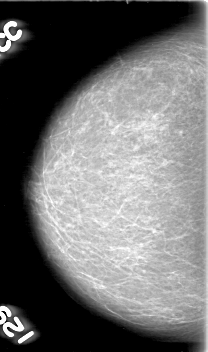

D_4055_1.RIGHT_CC

RIGHT_CC LINES 5266 PIXELS_PER_LINE 3106 BITS_PER_PIXEL 12 RESOLUTION 43.5 NON_OVERLAY